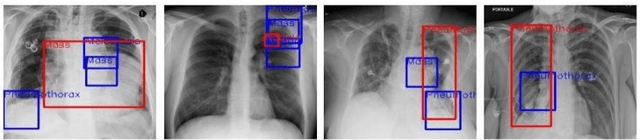

Abstract:Advancements in Telemedicine as an approach to healthcare delivery have heralded a new dawn in modern Medicine. Its fast-paced development in our contemporary society is credence to the advances in Artificial Intelligence and Information Technology. This paper carries out a descriptive study to broadly explore AI's implementations in healthcare delivery with a more holistic view of the usability of various Telemedical Innovations in enhancing Virtual Diagnostic Solutions (VDS). This research further explores notable developments in Deep Learning model optimizations for Virtual Diagnostic Solutions. A further research review on the prospects of Virtual Diagnostic Solutions (VDS) and foreseeable challenges was also highlighted. Conclusively, this research gives a general overview of Artificial Intelligence in Telemedicine with a central focus on Deep Learning-based approaches to Virtual Diagnostic Solutions.